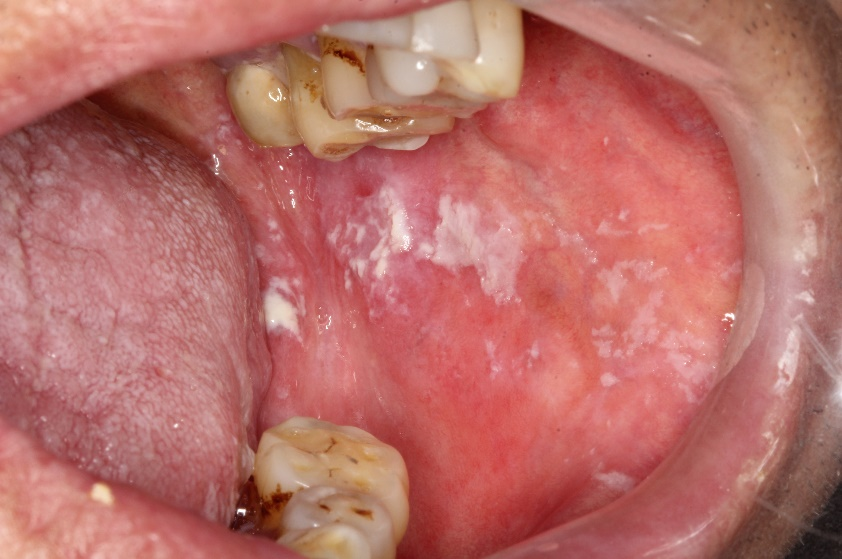

口腔念珠菌病图片

其中口腔念珠菌感染是艾滋病最常见的口腔病损,患病率为4.9%~83.

口腔念珠菌感染的病因,症状,临床表现和治疗

白色念珠菌口腔感染是怎样的?

口腔扁平苔藓的病因尚不明确,但可能与遗传因素,自身免疫,感染,精神